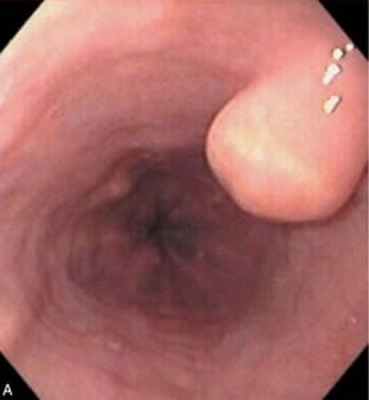

1. Папиллома (из многослойного плоского эпителия пищевода) — единичные или множественные папилломы имеют четкие, ровные или бугристые контуры с характерным внутренним рельефом (сосочковый, бородавчатый или шагреневый). Иногда выступающие в просвет пищевода папилломы напоминают цветную капусту. Опухоли растут на ножке или широком основании. Врожденные папилломы (папиллярная фиброма из эктопированных клеток) чаще выявляются в раннем возрасте, приобретенные обычно развиваются на фоне хронического эзофагита

Лейомиома пищевода — доброкачественная опухоль, которая выявляется в виде выбухающего в просвет округлого образования на широком основании с гладкой поверхностью и четкими границами, которая при инструментальной «пальпации» имеет плотноэластичную консистенцию и легко смещается. Лейомиомы растут в плотно-эластичной капсуле, рост медленный, слизистая оболочка под опухолью хорошо смещается, подвижна (это очень важный диагностический симптом). Как правило, слизистая над образованием не изменена, но в ряде случаев слизистая над опухолью может воспаляться вплоть до эрозирования и изъязвления. При выявлении лейомиомы, если слизистая над опухолью не изменена, биопсия не рекомендуется.